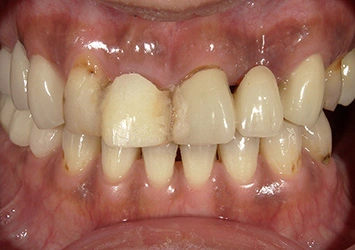

治療後

治療後写真 恵比寿南DENTAL 治療後写真 恵比寿南DENTAL

施術内容

【40代女性】

右上の前歯が歯根破折となっしまった為抜歯を行い、抜歯と同時にインプラント埋入を行った

治療期間

3ヶ月

リスク

術中の不可抗力によるトラブル(出血など)、術後注意事項を守らないことによる疼痛、感染、上部構造装着後口腔内清掃を怠ったことによるインプラント周囲組織の炎症

副作用

治療後の口腔内清掃、及びメインテナンスを怠ったことによるインプラント周囲粘膜炎またはインプラント周囲炎

費用

インプラント埋入:30万円

ジルコニアオールセラミッククラウン:15万円